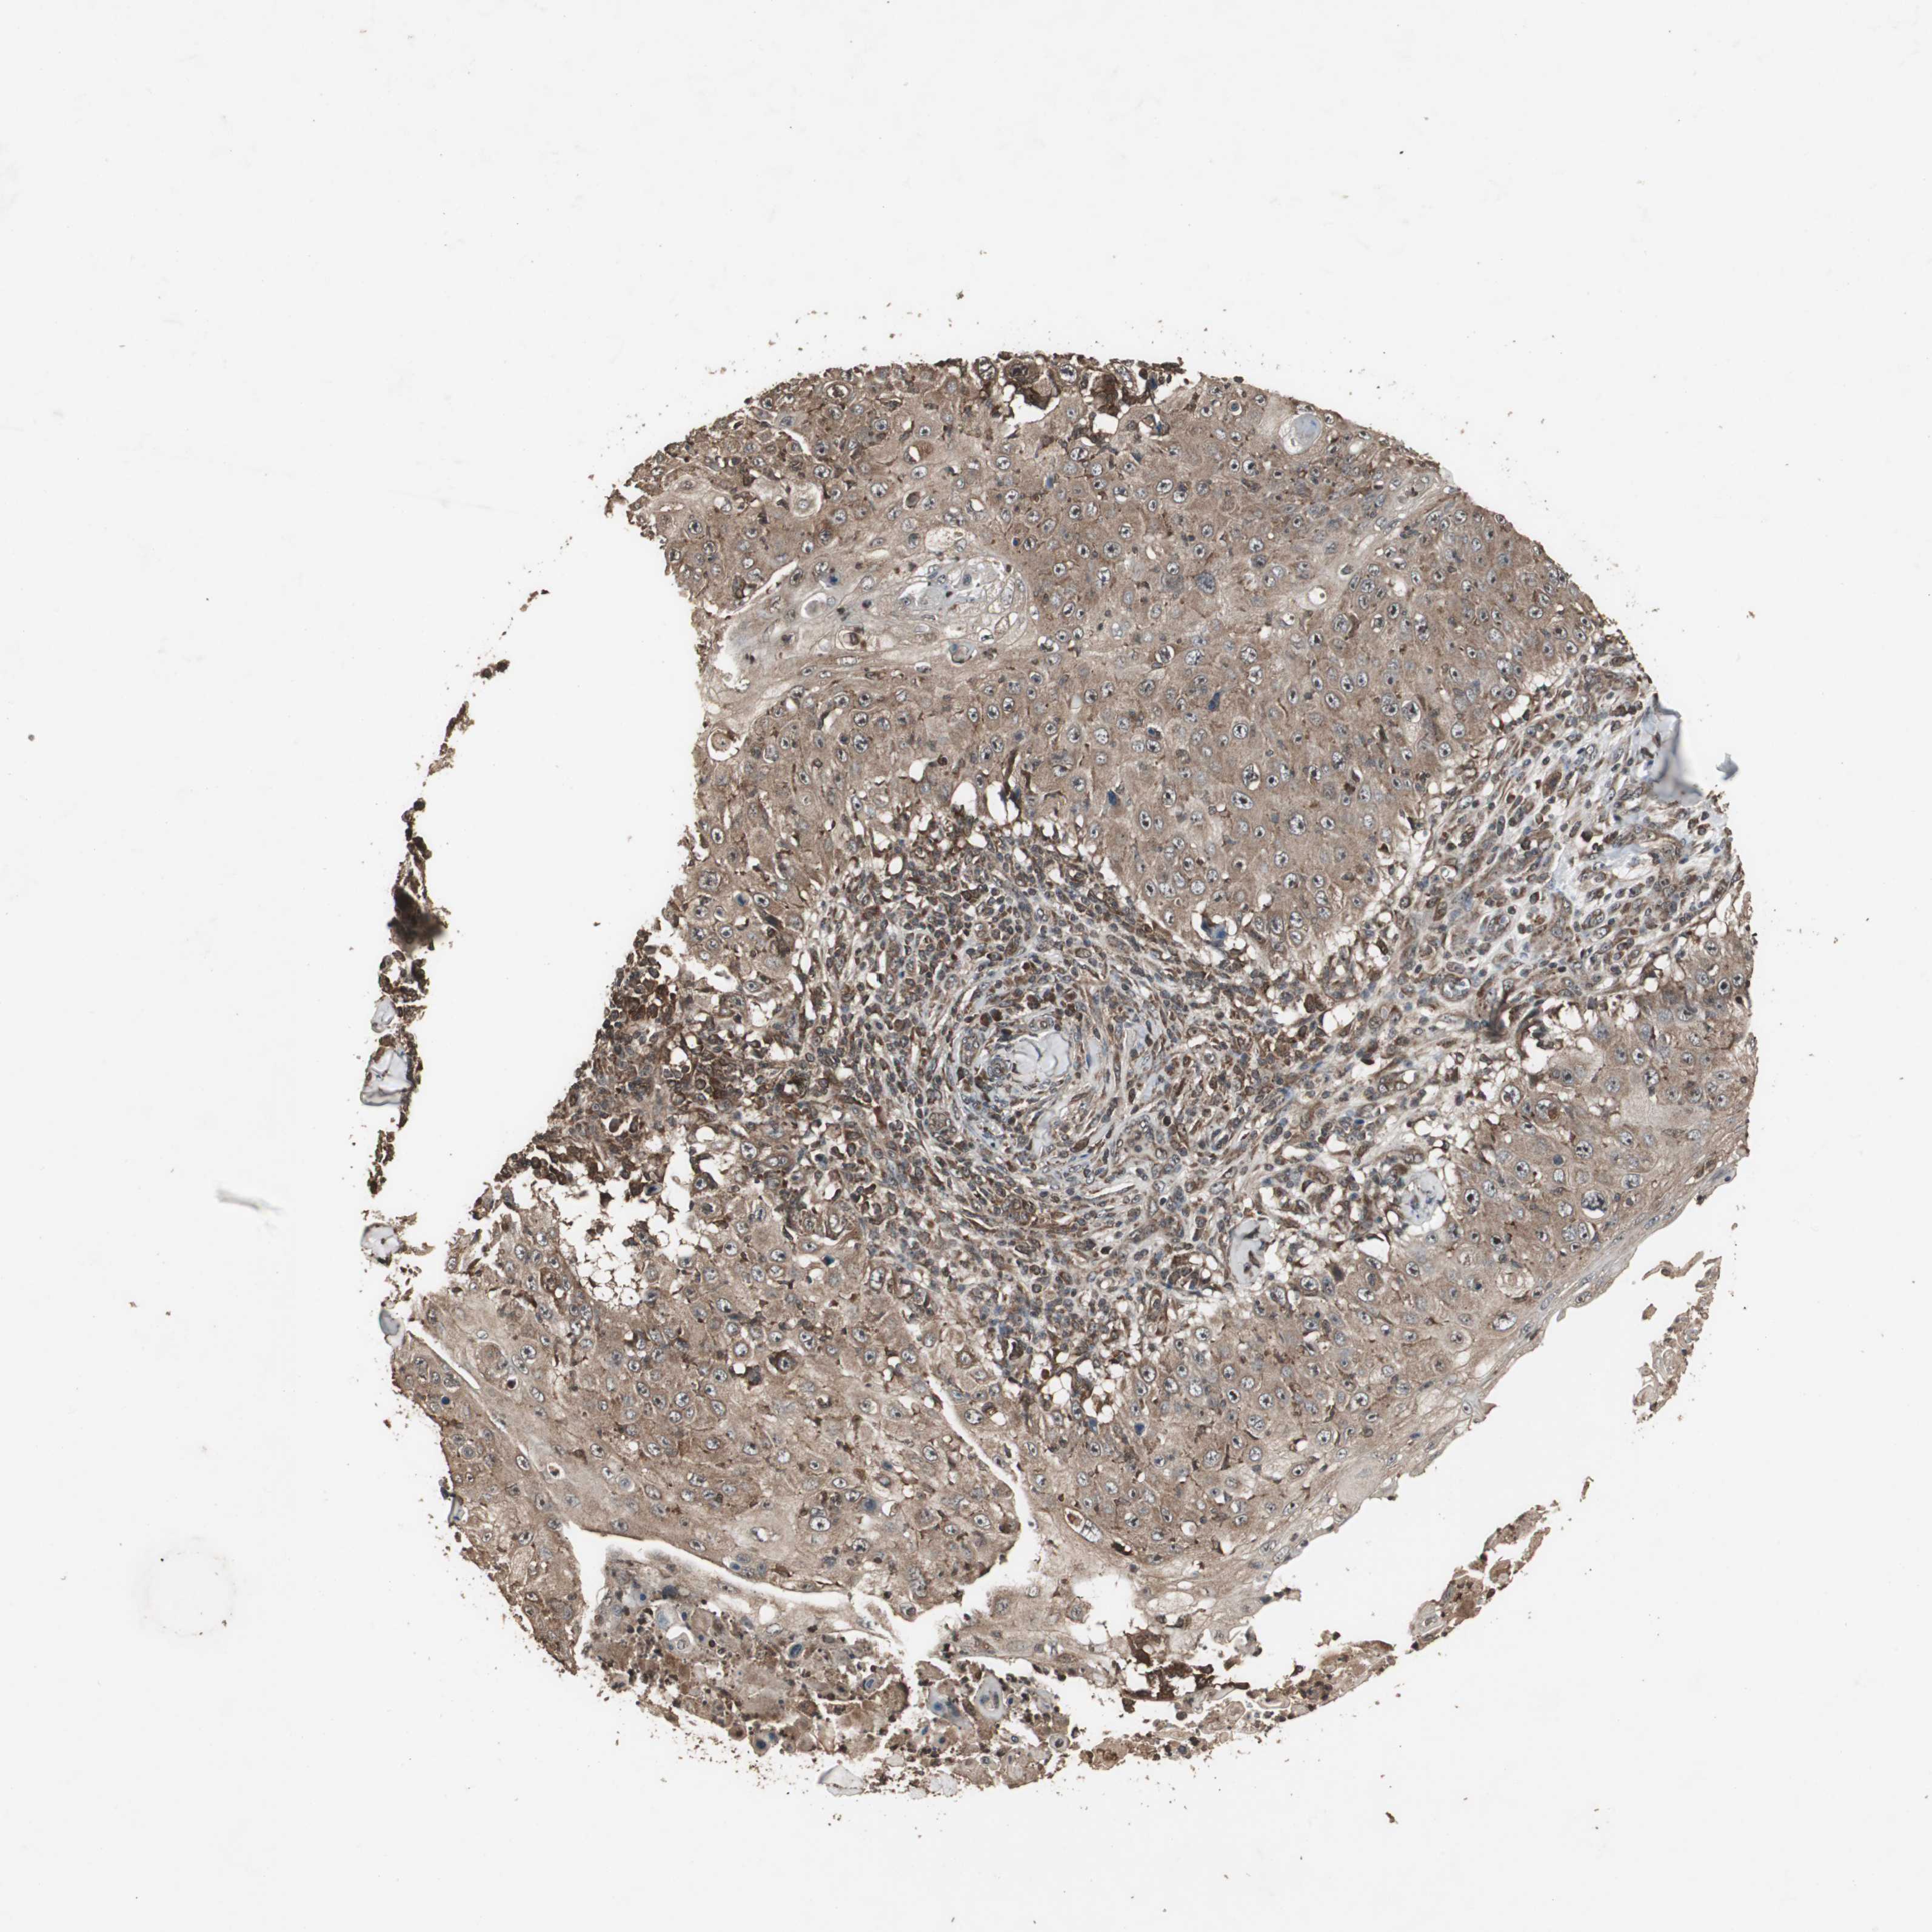

SKIN CANCER - Protein expressioni

A mouse-over function shows sample information and annotation data. Click on an image to view it in a full screen mode. Samples can be filtered based on level of antibody staining by selecting one or several of the following categories: high, medium, low and not detected. The assay and annotation is described here.

Antibody staining in the annotated cell types in the current human tissue is reported as not detected, low, medium, or high, based on conventional immunohistochemistry profiling in selected tissues. This score is based on the combination of the staining intensity and fraction of stained cells.

Each image is clickable and will lead to virtual microscopy that enables deeper exploration of all samples and also displays staining intensity scores, fraction scores and subcellular localization as well as patient and tissue information for each sample.

Antibody HPA006812

Staining

High

Medium

Low

Not detected

Intensity

Strong

Moderate

Weak

Negative

Quantity

>75%

75%-25%

<25%

None

Location

Nuclear

Cytoplasmic/membranous

Cytoplasmic/membranous,nuclear

Squamous cell carcinoma, NOS

Basal cell carcinoma